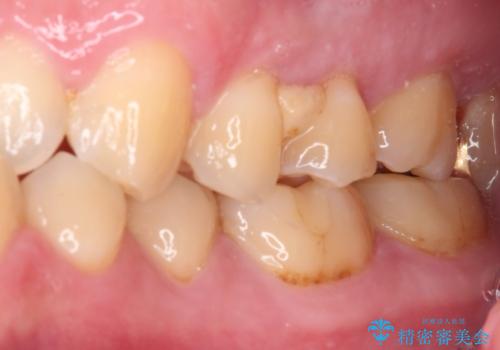

- 左右下顎の奥歯に違和感を感じるとのことで来院された患者様です。

最近ものが挟まりやすくなったり、冷たいものがしみるようになったりと言った症状があり、診査したところ、歯質の欠損や不適修復物などが認められました。

精度の高いセラミックインレーによる修復治療が第一選択となりますが、一方の歯は元々修復物が大きく、咬合力の強い方であったので、セラミッククラウンによる補綴治療を行うこととしました。